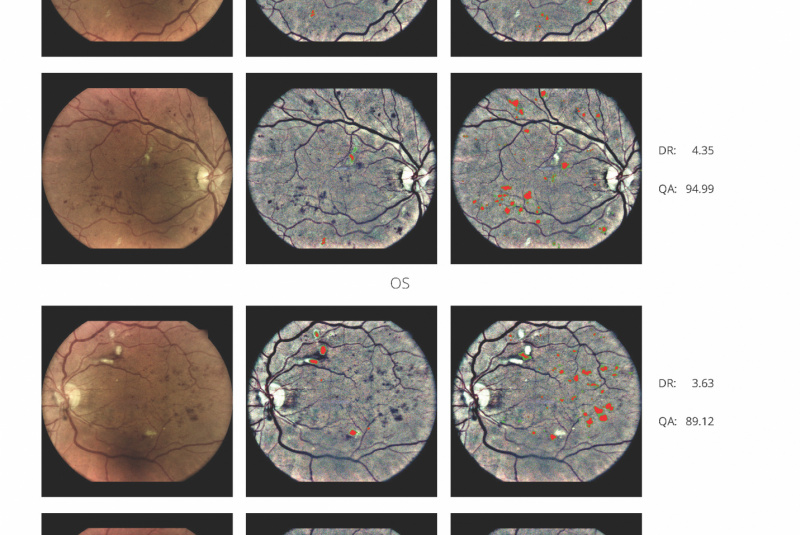

AI (umělá inteligence) okamžitě rozpozná příznaky diabetické retinopatie a klasifikuje výsledky podle závažnosti na základě mezinárodní klasifikace. Získáte přehled s hodnocením závažnosti zachycení, kdy se po analýze snímků pořízených kamerou iCare DRSplus automaticky vygeneruje zpráva pro pacienta se stupnicí závažnosti diabetické retinopatie na základě mezinárodních standardů (ICDR, AREDS).

Fundus kamera iCare DRSplus pořídí celkem 4 vysoce kvalitní snímky TrueColor (dva z pravého a dva z levého oka), které se automaticky uloží do cloudu a odešlou ke zpracování umělé inteligenci - AI. Zpráva je k dispozici okamžitě a může být zkontrolována s pacientem během téže návštěvy lékaře.

Software RetCAD

- schopnost zhodnotit téměř 100 % snímků

- Výsledek na škále 0-4 podle ICDR

- International Clinical Diabetic Retinopathy

(medzinárodní klinická škála závažnosti diabetické retinopatie) - Výsledek generovaný na základě 2 snímků z každého oka

(centrální a nazální)

Medzinárodní oftalmologický standard vyžaduje

výsledek podla min. 2 snímků z každého oka.